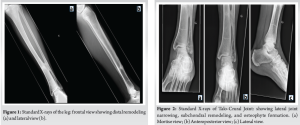

The causative fracture was a left tibia-fibula fracture in early childhood due to a road traffic accident, treated conservatively with casting. The lateral malleolar fracture was insufficiently reduced, resulting in significant fibular shortening. The 57-year-old patient presented with chronic lateral-dorsal pain in the left ankle, clinically accompanied by hindfoot valgus deformity and limited mobility with a submalleolar and anterior ankle impingement. The X-rays show bone remodeling and tibiofibular arthrodesis at the distal third (Fig. 1). Additional imaging included scintigraphy showing progressive tibio-talar osteoarthritis and early-stage Lisfranc joint osteoarthritis (Fig. 2). MRI and CT confirmed post-traumatic fibular shortening, consequent hindfoot valgus, and partially misaligned tibio-talar osteoarthritis in the lateral compartment (Figs. 3-5). Surgical management was indicated for the angular malunion, involving medializing calcaneal osteotomy and fibular lengthening osteotomy on the left ankle. Preoperative planning included standing anteroposterior (AP) and lateral radiographs of the ankle and hindfoot, as well as hindfoot alignment views (Saltzman view) to assess coronal malalignment. Full-length standing radiographs of both lower limbs were obtained to evaluate the mechanical axis. CT scan was used to precisely measure the degree of fibular shortening and tibiofibular joint fusion. MRI allowed for soft tissue and cartilage evaluation, particularly at the tibio-talar joint. Fibular shortening was assessed by comparing the level of the lateral malleolus to the plafond tibial and to the medial malleolus on the contralateral, uninjured side. Correction planning aimed to restore the fibular length to reestablish the normal relationship, targeting the lateral malleolus tip approximately 5–7 mm distal to the talar dome on the mortise view, which corresponds to the physiological fibular station. Angular correction involved planning for a 10° medial translation at the calcaneus level to correct the hindfoot valgus, based on hindfoot alignment measurements. Five weeks later, arthroscopy was performed for osteophyte removal as a second stage. The surgical procedure involved a Z-lengthening osteotomy of the , achieving approximately 9 mm of lengthening, fixed with two compression screws and a neutralization plate, supplemented by a corticocancellous graft harvested from the left anterior iliac crest (Fig. 6). The medializing calcaneal osteotomy required a medial displacement of the large tuberosity by 10 . The 10-mm medial shift was determined based on hindfoot alignment analysis, correcting approximately 1 mm/degree of valgus. This was achieved through lateral cortical osteotomy with the saw and medial completion with an osteotome, then fixed with two partially threaded titanium 7.0 compression screws (FixosR, Stryker, Mahwah, NJ 07430 USA) (Fig. 7). The surgery was performed under scopic guidance. Postoperatively, the non-weight-bearing period extended to 5 weeks, followed by an arthroscopy for osteophyte removal performed after the cast immobilization period. Physiotherapy was initiated 2 weeks later, following suture removal, with full weight-bearing allowed using a stabilizing ankle brace. No intra-operative or early postoperative complications were reported. Postoperative radiographs obtained at 6 weeks and at the final follow-up (24 weeks) illustrate satisfactory healing and a favorable clinical outcome (Fig. 8).